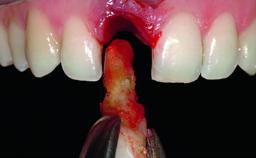

Replacement of an Upper Right Central Incisor with Root Resorption: Ridge Preservation, Early Placement of an RC Bone Level Implant

A 49-year-old female patient was referred for implant therapy to replace the upper right central incisor (tooth 11). The tooth had been assessed by an endodontist who diagnosed a vertical fracture of the root. The tooth had a hopeless prognosis and needed to be extracted. The patient was healthy and was not taking any medications. She was allergic to penicillin. The patient had high esthetic demands but her expectations were realistic. The extraoral examination revealed no facial asymmetries. The right temporomandibular joint demonstrated an opening click but was otherwise asymptomatic. The lip line was high with a significant gingival display.